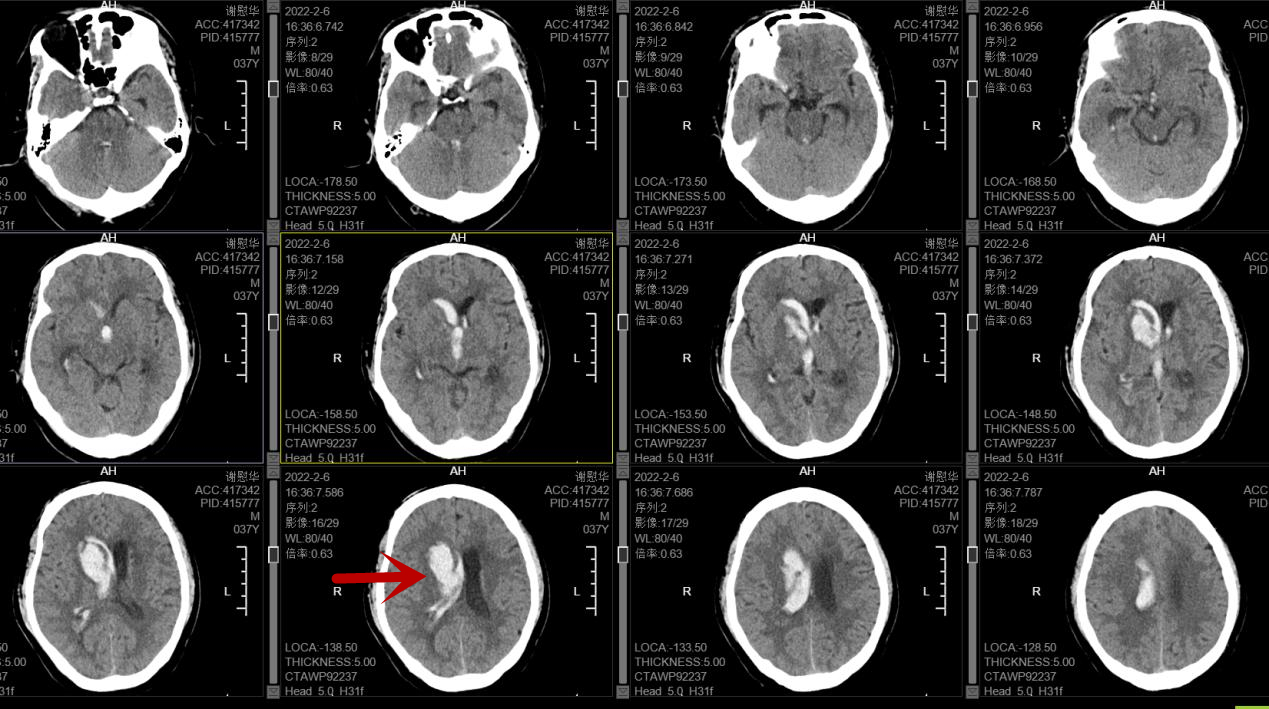

术后头颅CT(微创精准置管--箭头所指的两个小白点)

在王智勇主任及神经外科团队的相互配合下,成功为阿志施行三维定向置管微创手术,术后第二天,阿志逐渐恢复神志,经过持续引流和注射药物溶解淤血块等综合治疗,他的病情也逐步稳定好转,颅内出血基本吸收,可自行站立,左侧肢体力量也逐渐恢复到发病前状态并顺利出院。近日复诊时,阿志病情基本康复,未遗留明显的后遗症。